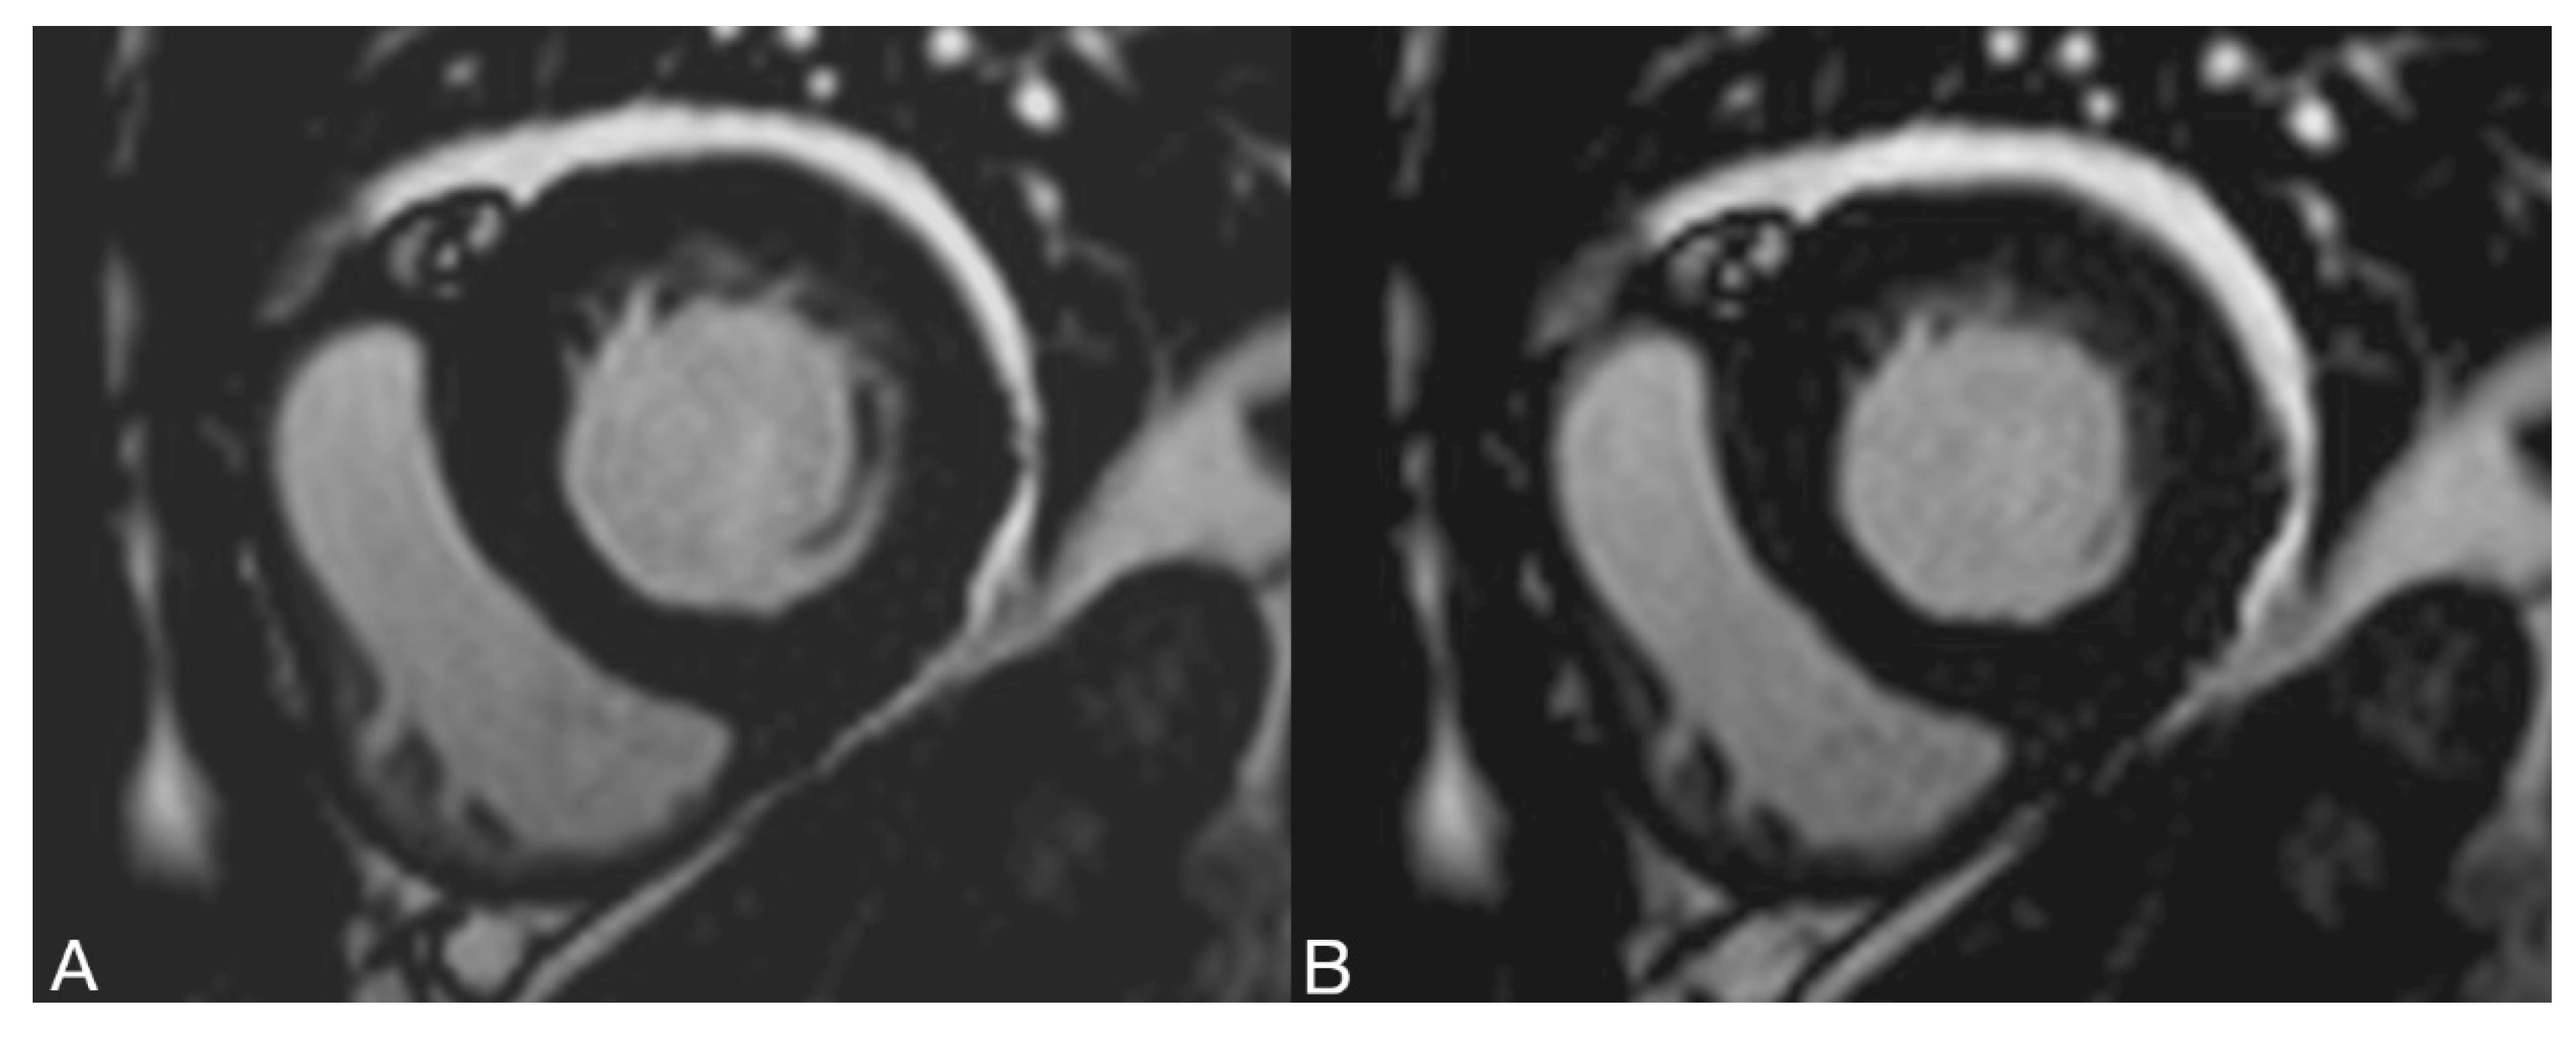

2.2. Examination Technique

2.2.1. MR Parameters